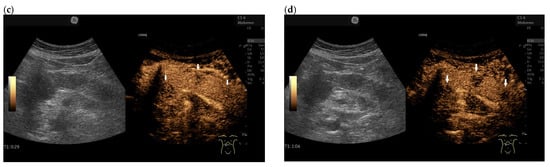

3.4. CEUS and CH-EUS

| Colour Doppler Imaging | RCC metastases are hypervascularized Most other pancreatic metastases are hypovascularized | No hypervascularization | Hypervascularized |

| Cases | CEUS | CH-EUS | ||

|---|---|---|---|---|

| Arterial Phase | Venous Phase | Arterial Phase | Venous Phase | |

| RCC metastases [83] (n = 4) | Hyperenhancement, Early | Hyperenhancement | ||

| RCC metastases [61] (n = 3) | Hyperenhancement, homogeneous pattern | Slow washout | ||

| RCC metastasis [86] (n = 1) | Hyperenhancement, Inhomogeneous pattern | No washout | ||

| Melanoma metastasis [63] (n = 1) | Iso- to slightly hypoenhanced | Hypoenhanced | ||

| Melanoma metastasis [87] (n = 1) | Isoenhanced | Hypoenhancement of the peripheral rim, central non-enhancement | ||

| Melanoma metastasis [61] (n = 1) | Isoenhanced, heterogeneous | Fast washout | ||

| SCLC metastasis [83] (n = 1) | Hyperenhancement | Rapid washout | ||

| Breast, ovarian, colon metastases, sarcoma metastases [61] (n = 6) | Hypoenhancement, homogeneous or heterogeneous | Fast or slow washout | ||

| Lymphoma metastasis [61] (n = 1) | Hyperenhancement, homogeneous pattern | Fast washout |